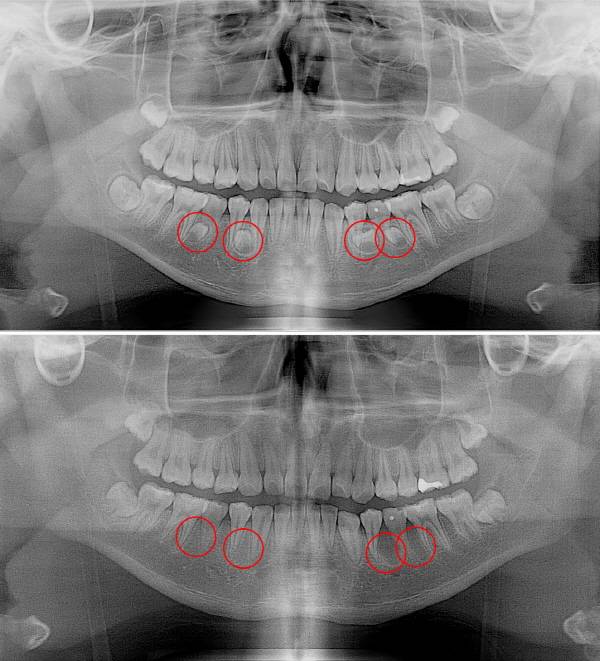

과잉치는 대다수 턱뼈 내에 매복돼 있어 당사자가 미리 알기는 매우 어렵다. 파노라마 방사선 촬영과 근단 방사선 사진 촬영, CT (컴퓨터단층촬영) 등을 통해서만 발견할 수 있다. 부모나 형제에게 과잉치가 있으면 발생 확률이 높아지므로, 확인해 보는 것이 좋다. 아직 과잉치가 발생하는 정확한 원인은 밝혀지지 않았다.

과잉치를 방치하면 치아가 잇몸을 정상적으로 뚫고 올라오지 못해 치아 배열이 흐트러진다. 앞니가 나오는 것을 방해해 앞니가 아예 못 나올 수 있다. 이상한 위치로 나와 부정교합을 유발해 저작 기능을 떨어뜨리기도 한다. 턱뼈에 매복해 알아차리기 어려운 과잉치는 제거하지 못하고 오랫동안 남아있게 되면 주변에 낭종을 유발할 수 있다. 고려대 안산병원 구강악안면외과 임재형 교수는 “과잉치는 영구치의 맹출을 방해해 치열이 흐트러지게 하고, 심한 경우 과잉치가 주변 정상 치아의 치근을 흡수하는 합병증을 유발해 드물게는 낭종, 종양 등의 병소를 유발할 수도 있어 결코 가벼이 넘길 수 없는 질환이다”라며 "특히 영구치가 자리 잡는 6~15세에 주의해야 한다"고 했다.

치아를 감싸고 있는 치낭에 물이 차는 함치성낭종이 합병증으로 유발되면, 턱뼈가 서서히 녹거나 다른 치아의 위치가 바뀌어 ▲턱뼈 골절 ▲골수염 ▲양성종양 등으로 이어질 수 있다. 또 치아 주변에 과잉치로 고름이 생기면 목 등으로 퍼져 각종 악안면부에 감염이 생길 수도 있다.